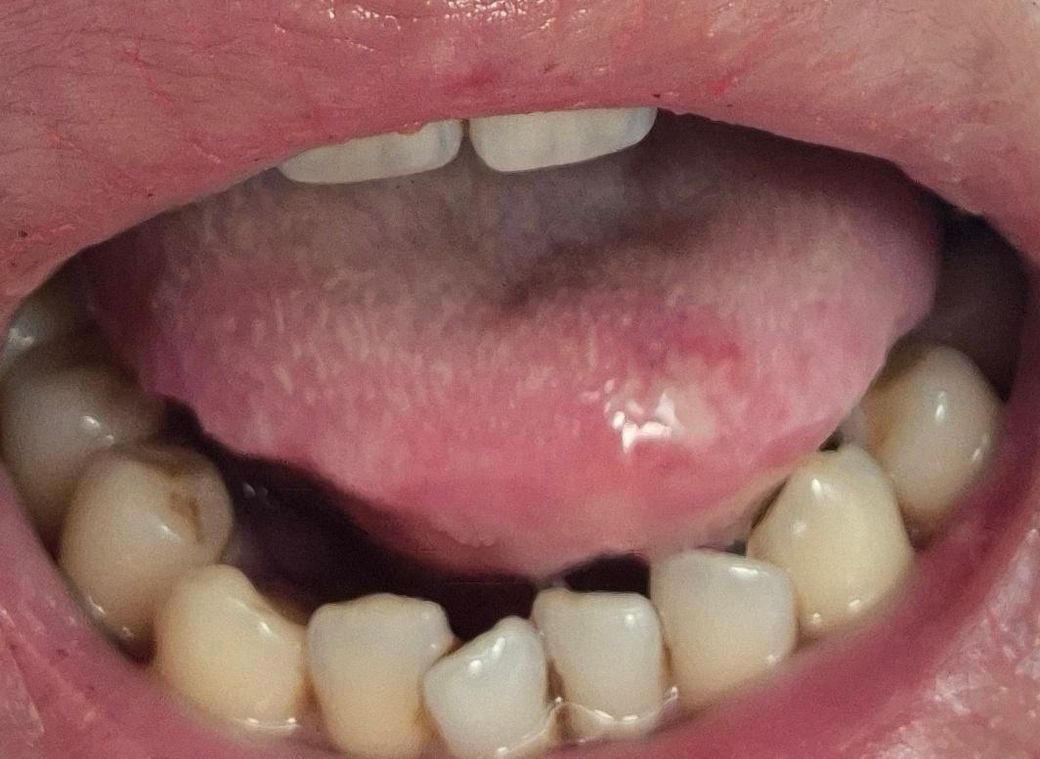

• 1번 째 사진